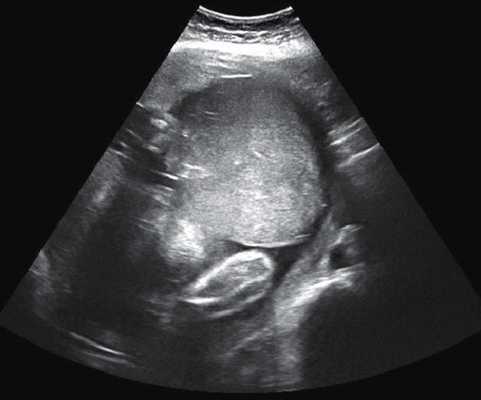

УЗИ помогает выявить начальные признаки ПОНРП и решить вопрос о срочном родоразрешении, однако при яркой развернутой картине это исследование ведет только к потере драгоценного времени. Окончательно степень тяжести ПОНРП определяется ретроспективно, то есть после визуального осмотра плаценты.

- УЗИ матки. Между плацентой и миометрием определяется эхо-негативная зона. Можно приблизительно рассчитать площадь отделившегося участка плаценты. Сердцебиение плода сохраняется до момента его гибели, но двигательная активность снижена. Шейка матки сомкнута, нормальной длины.